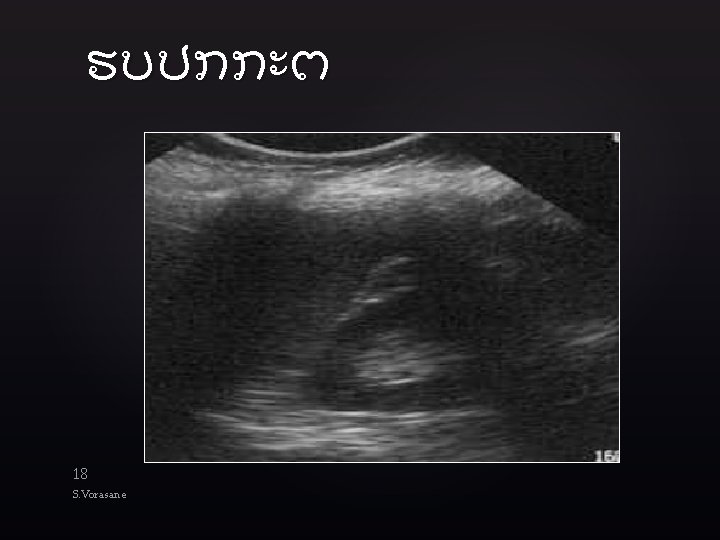

Technique l Goal: to identify blood in body cavities where it is not supposed

Technique l Goal: to identify blood in body cavities where it is not supposed to be l l Unclotted blood appears black on US Clotted blood appears gray Abdominal probe with small footprint (between 13 cm) with range of frequency between 2. 0 Hz and 5. 0 Hz Scan 4 areas l l RUQ Subxiphoid LUQ Suprapubic